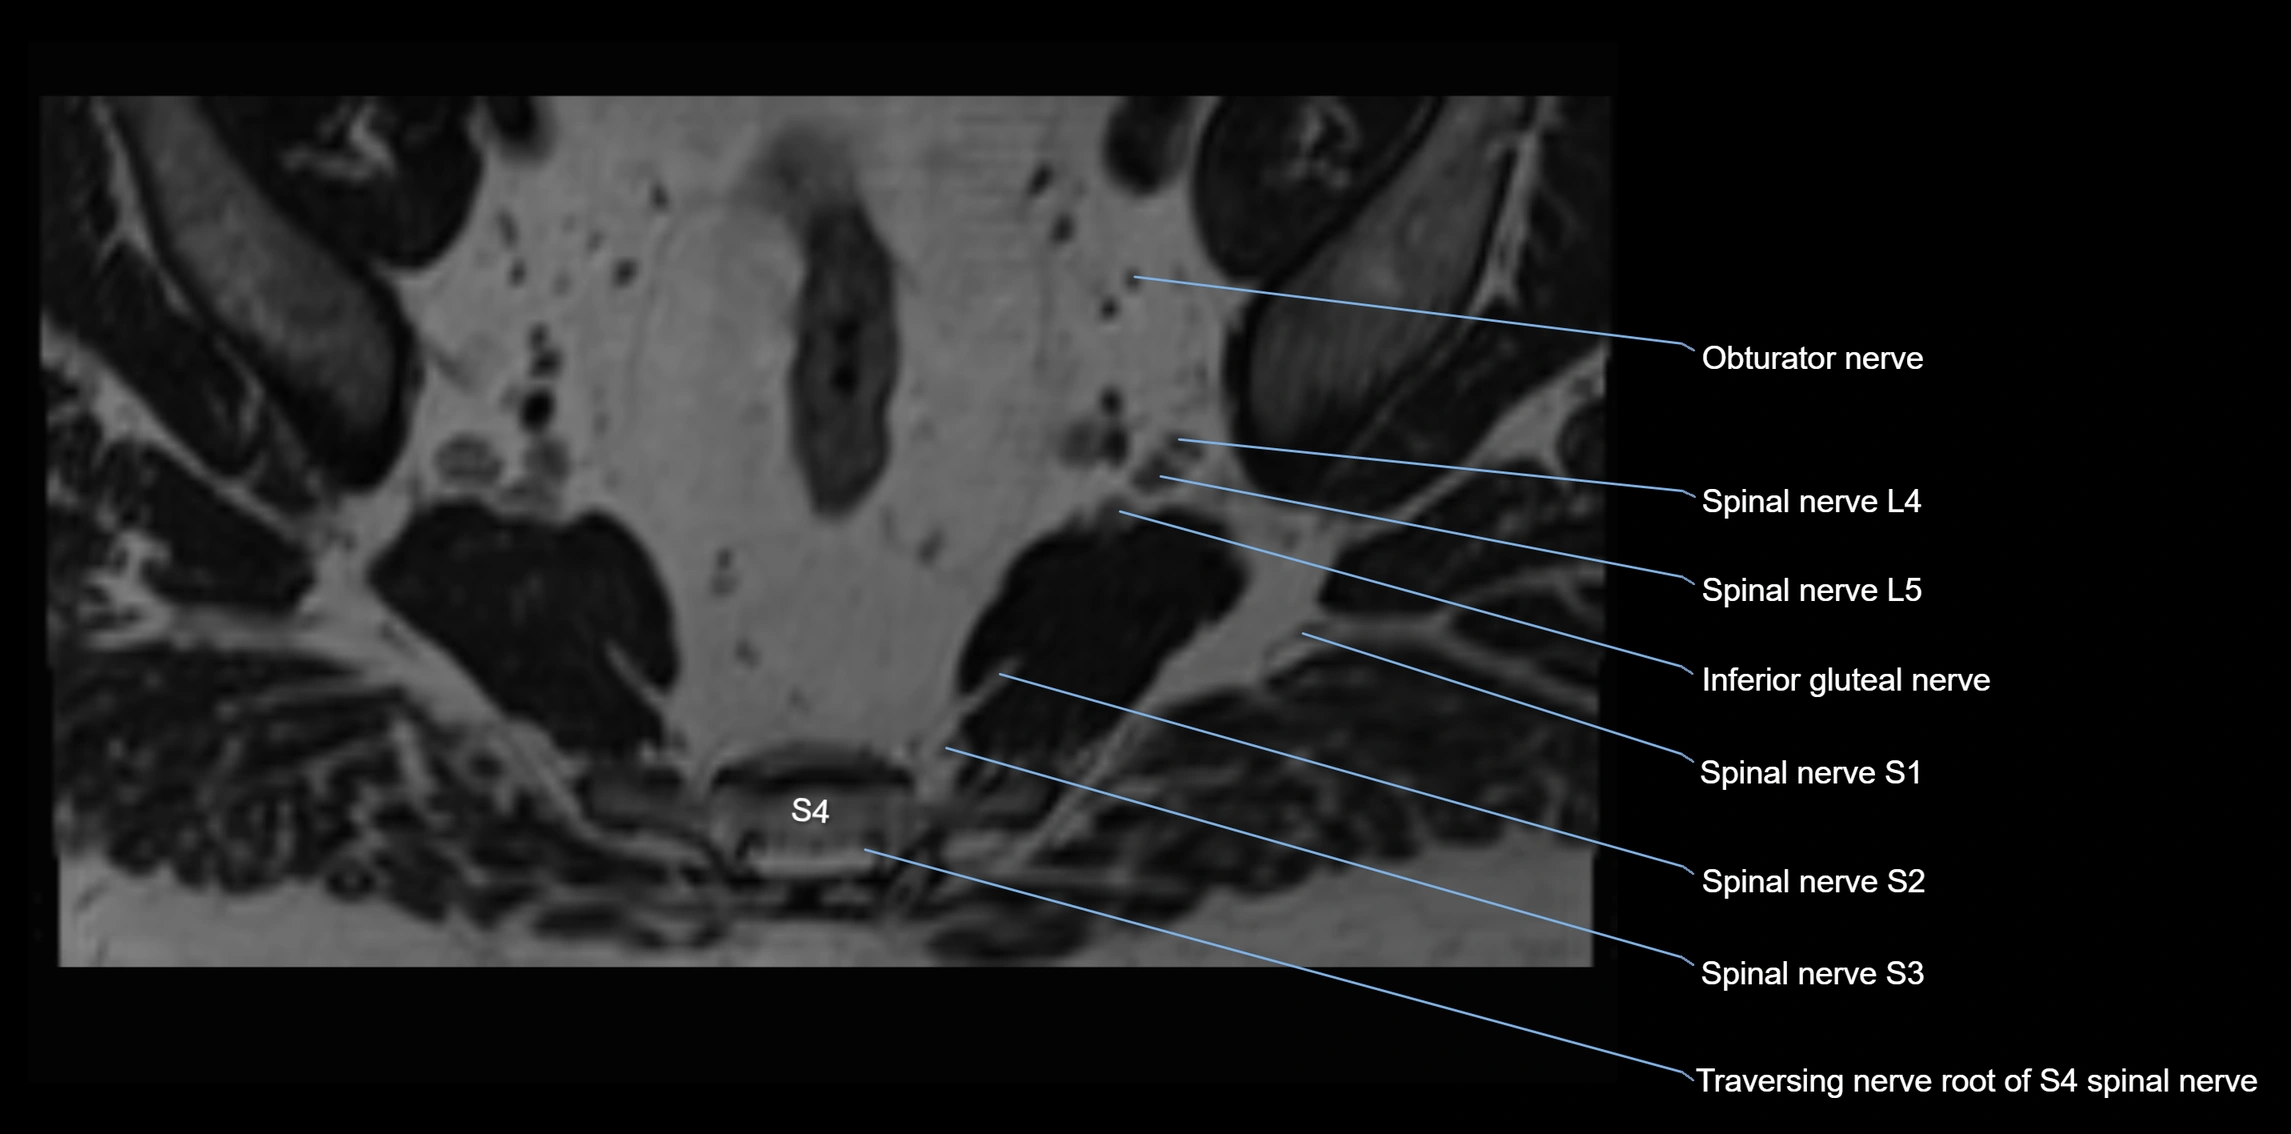

MRI image

image